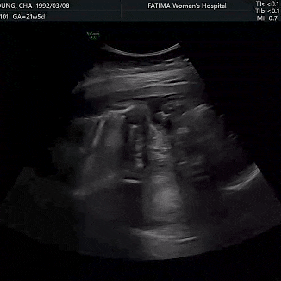

[둘째 임신기록]임신 21주차 기록 정밀초음파 잊었던 a형간염2차 세이베베 오류

오랜만에 산부인과 검진을 다녀왔다 떨리는 정밀초음파날! 21주 기록 배가..많이 나왔다 걷는데 뒤뚱뒤뚱 ...